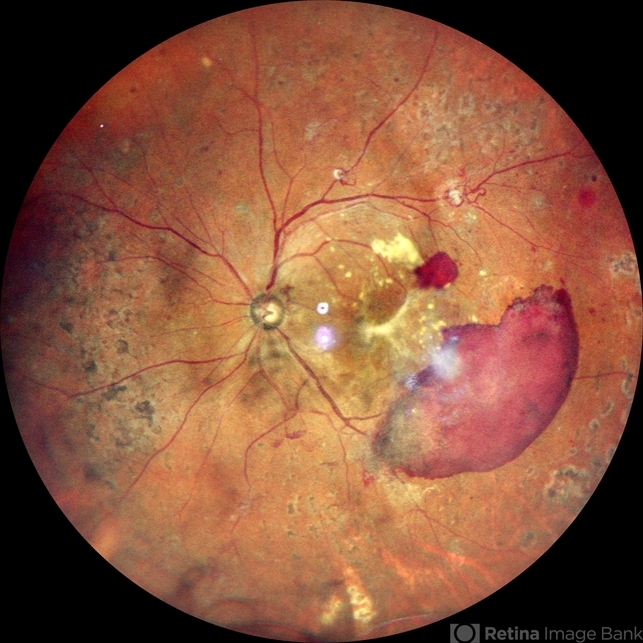

- proliferative diabetic retinopathy (PDR), pan-retinal photocoagulation (PRP)

- A widefield color image of a 60 year old male with type II diabetes showing sub hyaloid hemorrhage with traction at the fovea with hard exudates with venous looping along the supero temporal arcade with NVE inferiorly with surrounding laser marks.